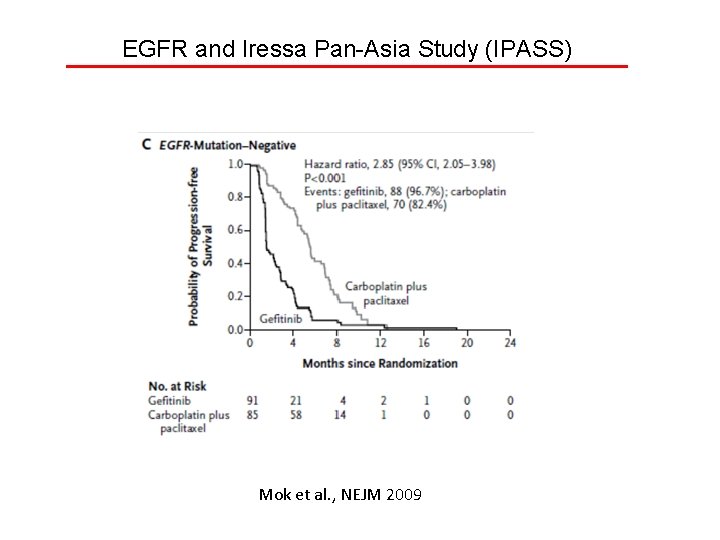

EGFR and Iressa Pan-Asia Study (IPASS) Mok et al. , NEJM 2009